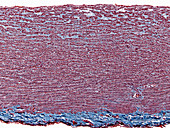

13416586 - Aorta tunica media and adventitia, light micrograph

12634941 - Aorta, tunica adventitia and media, LM

12634940 - Aorta, tunica adventitia and media, LM

12634939 - Aorta, tunica adventitia and media, LM